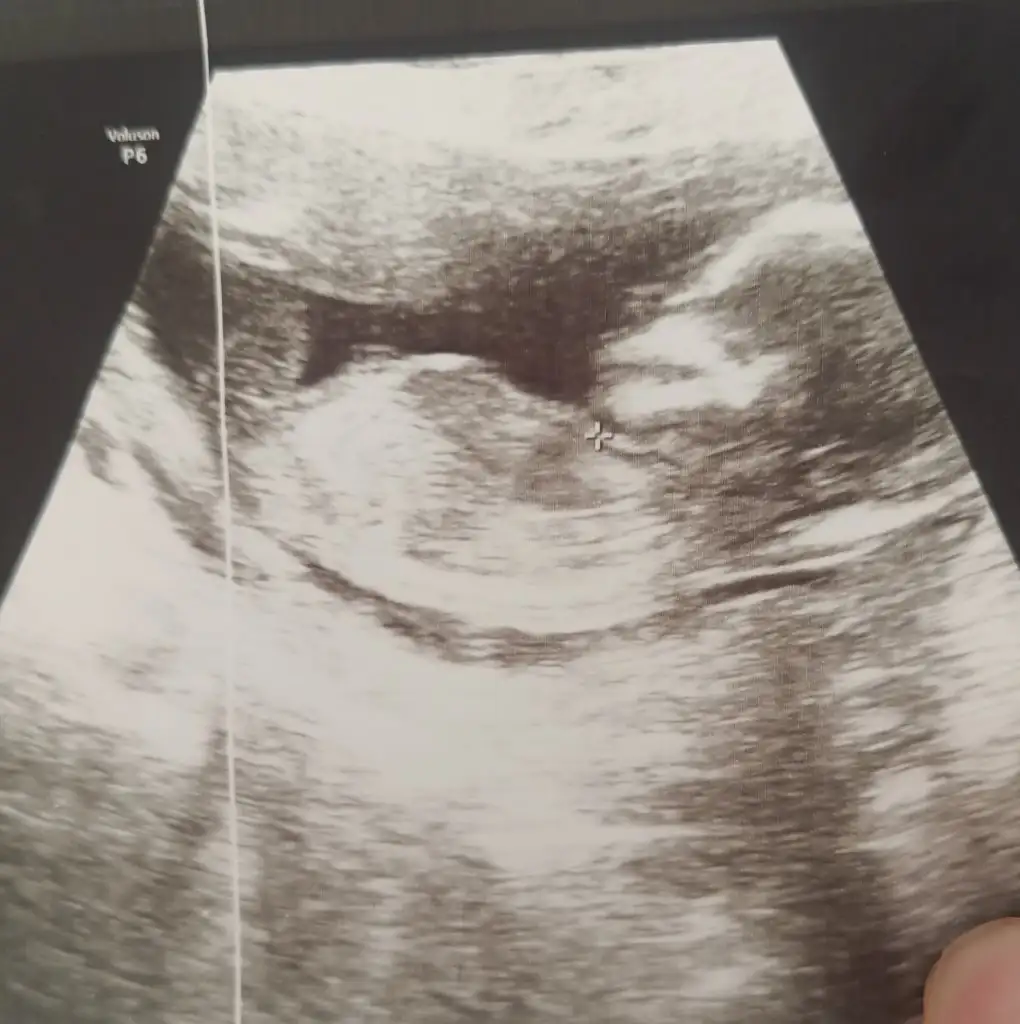

Buna da bi el atar mısınız kızlar 💐

B6D01CB2-03E5-4403-825E-F548C588EC1D.webp

• IMG_4372.webp

IMG_4372.webp

46,6 KB · Görüntüleme: 58

• 56a3683e-ea75-4941-a075-9b5f2c95039d.webp

56a3683e-ea75-4941-a075-9b5f2c95039d.webp

60,2 KB · Görüntüleme: 55